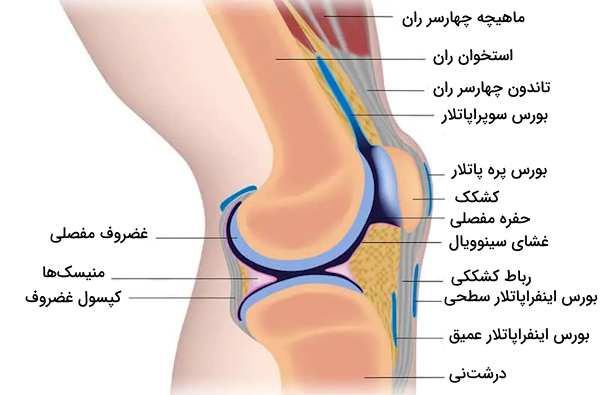

کپسول مفصل

کپسول مفصل زانو ماهیتی مرکب دارد که به طور عمده از تاندون ماهیچهها تشکیل شده است. گسترش تاندونهای ماهیچهای باعث ساخت یک غلاف رباطی ضخیم در اطراف مفصل میشود. این کپسول که به حاشیههای سطوح مفصلی استخوانهای ران و درشت نی متصل میشود، از لحاظ ساختاری به نسبت ضعیف به حساب میآید.

ساختار مفصل زانو را میتوان به دو بخش تقسیم کرد که در ادامه با آنها آشنا میشویم.

- لایه فیبری خارجی: این لایه پیوسته به تاندونهای مجاور است.

- غشای سینوویال داخلی: این بخش مسئول روانسازی سطوح مفصلی، کاهش اصطکاک بین آنها و تامین مواد مغذی مورد نیاز غضروفها است.

کپسول مفصل چندین ساختار کیسهای ایجاد میکند که مملو از مایع هستند و «بورس» (Bursae) نام دارند. بورسها اصطکاک درونی مفصل زانو را کاهش میدهند. در ادامه با چهار بورس شاخص موجود در آناتومی مفصل زانو بیشتر آشنا میشویم.

- «بورس سوپراپاتلار» (Suprapatellar Bursa): در بالای کشکک بین استخوان ران و تاندون ماهیچه چهارسر ران قرار دارد.

- «بورس پره پاتلار» (Prepatellar Bursa): در جلوی کشکک بین این استخوان و پوست قرار گرفته است.

- «بورس اینفراپاتلار» (Infrapatellar Bursa): زیر کشکک بین رباط کشککی و استخوان درشتنی واقع شده است.

- بورس نیمغشایی یا «بورس سمیممبرانوس» (Semimembranosus Bursa): در پشت مفصل زانو، بین ماهیچه نیمغشایی و سر داخلی ماهیچه دوقلو قرار دارد.

رباط کشککی

رباط کشککی نواری فیبری است که از ادامه بخش انتهایی تاندون عضله چهارسر ران ایجاد میشود. این رباط ضخیم و مقاوم در بخش سطحی یا جلویی بورس زیرکشککی دیده میشود. به طور دقیقتر میتوان گفت که محدوده مربوط به رباط کشککی از نوک کشکک آغاز شده و تا «برجستگی استخوان درشت نی» (Tibial Tuberosity) ادامه مییابد. رباط کشککی نقش مهمی در تثبیت کشکک و جلوگیری از جابجایی آن ایفا میکند.